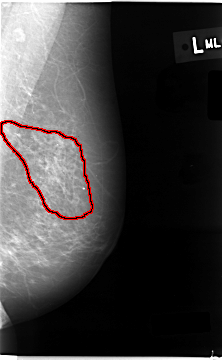

FILE: C_0007_1.LEFT_MLO.OVERLAY

TOTAL_ABNORMALITIES 1

ABNORMALITY 1

LESION_TYPE CALCIFICATION TYPE AMORPHOUS DISTRIBUTION REGIONAL

ASSESSMENT 5

SUBTLETY 5

PATHOLOGY MALIGNANT

TOTAL_OUTLINES 1

BOUNDARY